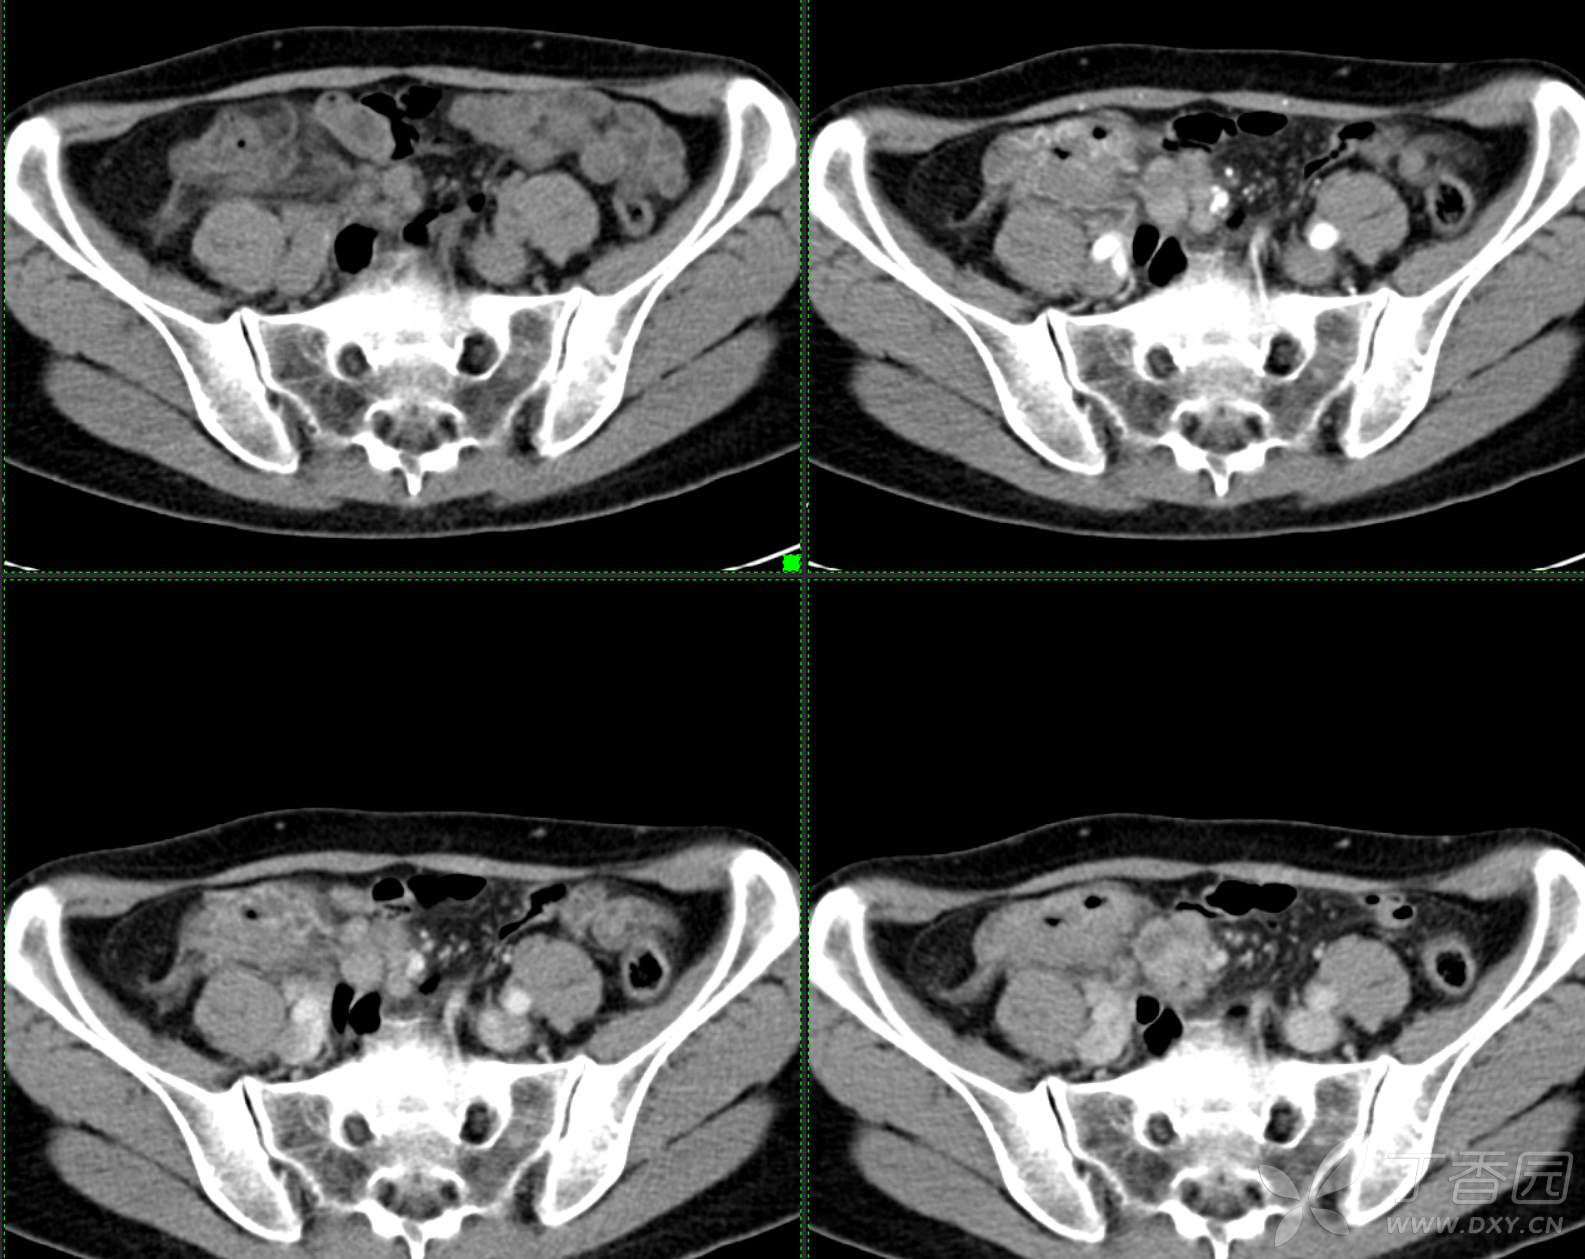

腹组13:患者,女,62岁,大便习惯改变2月余

主 诉: 【大便性状改变2月余】

现病史: 患者2月余前无明显诱因下出现大便次数增多,无明显血便黑便及粘液脓血便,大便次数由1次/日增加至2-3次/日,大便形状变细如小指,偶稀软不成形,无腹痛腹胀腹泻,无恶心呕吐、胸闷气促,肛门排气通畅,无发热盗汗。至当地医院就诊,行肠镜检查发现"回盲部占位"。为进一步治疗,我院门诊拟"回盲部肿瘤"收住入院。